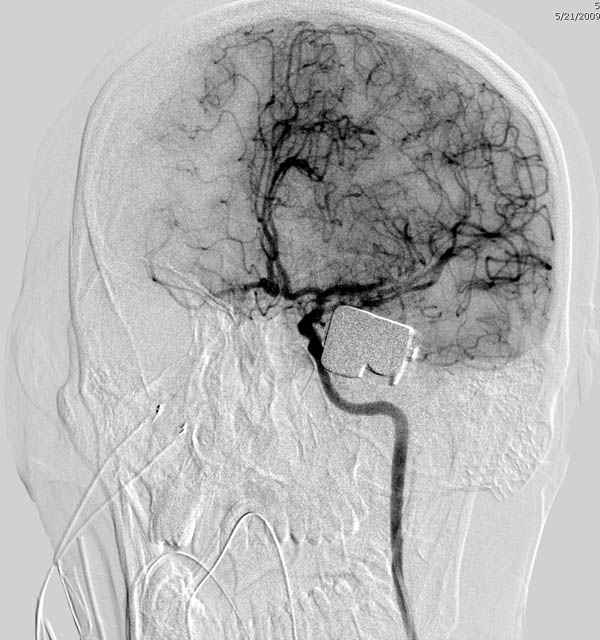

В своих выступлениях я рассказывал, что наши центры в мирное время по пенетрирующим травмам не уступает Ираку или Афганстану, и вот недавно к нам поступила больная 22 лет, травма "ножом в глаз" от бывшей подруги нынешнего "бой френда".

При поступлении в сознании, жаловалась на неприятные ощущения в глазнице.

По протоколу сделаны все необходимые исследования: рентген, ангиограмма с 3Д реконструкцией, где обнаружили что все жизненно важные сосуды не задеты, даже некоторые "сидят" изгибаясь на ноже.

Одним махом нож удалить не удалось, пришлось раскачать и потом двумя руками удалили нож. Рана без кровотечения, обработана и зашита.